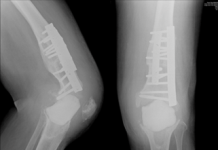

A one-two punch against knee osteoarthritis

A minimally invasive surgery combined with an autologous adipose stem cell transplant achieves a remarkable 88% cartilage regeneration rate.

Infections after avoidable knee replacement surgeries

With the implementation of the KHPO, knee replacement surgeries would have been unnecessary, sparing patients from significant suffering

Returning to an active life with knee osteoarthritis

Here Open Access Government explore a testimonial from a patient who received a “wonder” therapy for his knee osteoarthritis (OA).